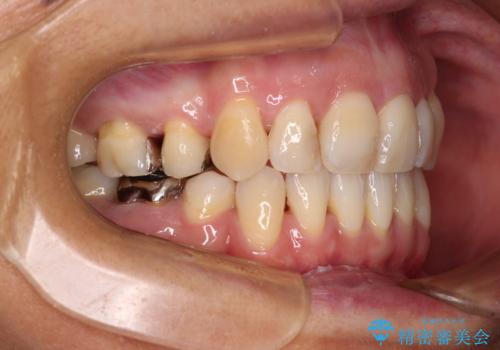

- 八重歯と、それによる口元の膨らみを気にして来院された患者様です。

八重歯・デコボコの解消とともに、前方に張り出した上顎前歯を引っ込めることを目的とし、上下左右の第一小臼歯4歯を抜歯をしてワイヤー矯正により治療することとしました。